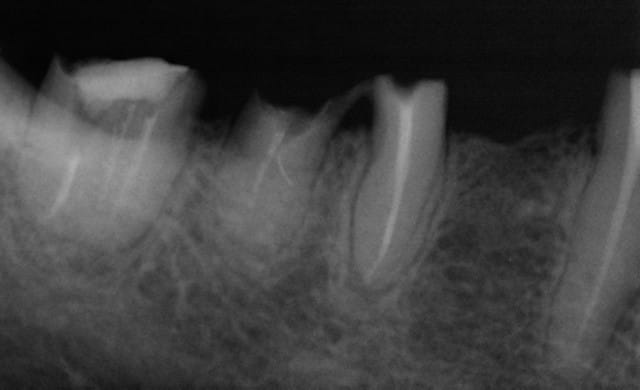

Cette même patiente, pimpante pour ses 90 ans et pleine de gaieté, viens me voir pour son nouvel appareil du bas qu'elle ne supporte pas. Avec surprise, je découvre dessous des chicots abandonnés par son ancien dentiste avec des inflammations gingivales. Radios prises, je lui propose de tenter de les récupérer pour lui réaliser des bridges en remplacement de son appareil, à l'inverse de ce qui se fait habituellement.

La racine résiduelle de la 37 était logée au fond d'un entonnoir gingival au ras de l'os et la 46 était trop délabrée pour la conserver entière. Après quelques séances de gingivoplasties et de tailles, le pari était gagné et les bridges ont pu être scellés, la patiente était radieuse!